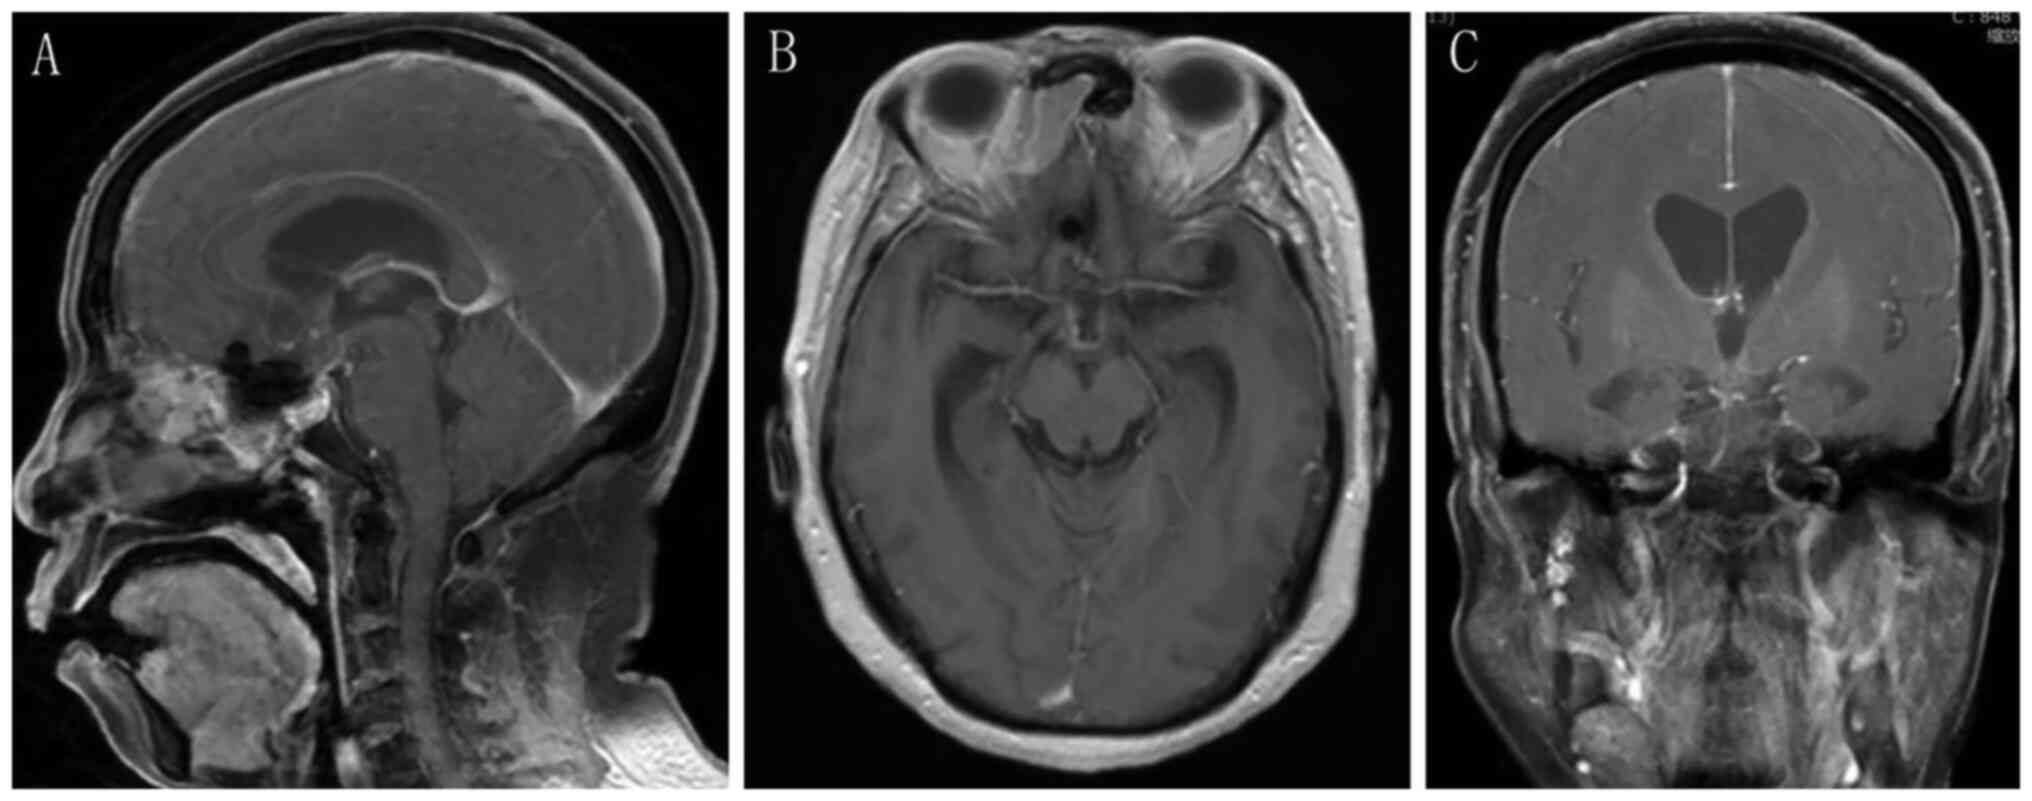

Craniopharyngioma resection and aneurysm clipping performed simultaneously by pure endoscopic endonasal approach: A case report and literature review

Craniopharyngioma is one of the most challenging issues for neurosurgeons as a brain tumor. Among the approaches of neurosurgery, in comparison to craniotomy, the endoscopic endonasal approach (EEA) has risen in popularity over the last two decades; unruptured intracranial aneurysms are relatively commonly found in the general population. The EEA as a new paradigm in the treatment of aneurysm has been reported to successfully clip dozens of cases of intracranial aneurysm. However, when reviewing the domestic and foreign literature, it appeared that cases of craniopharyngioma complicated with intracranial aneurysm purely treated by EEA have not been reported so far. In the present study, the published literature regarding endoscopic endonasal surgery for craniopharyngioma and intracranial aneurysms was reviewed, accompanied with a case of craniopharyngioma complicated with intracranial aneurysm, both of which were simultaneously treated by EEA.